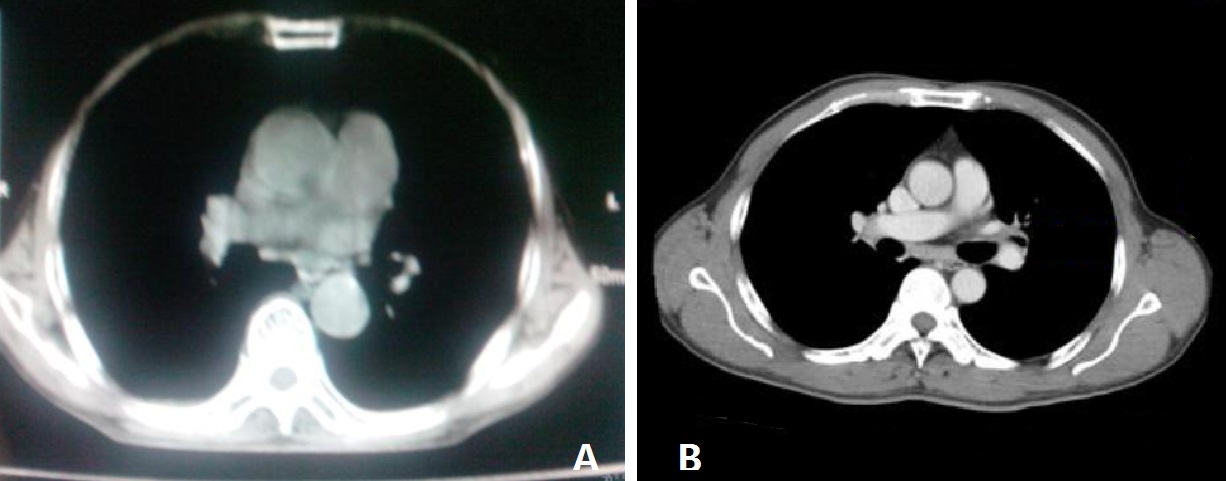

图5 ,幼儿与成人胸部CT 对比。A 为幼儿,B 为成人。正常幼儿胸廓已经为桶状,因此不能将其诊断为桶状胸。